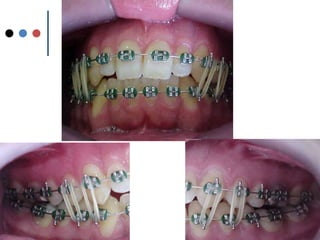

O documento apresenta registros odontológicos de um paciente ao longo de vários anos, incluindo panorâmicas iniciais e subsequentes, remodelações de arcadas dentárias superiores e inferiores ao longo de 7 meses, vedamentos labiais e registros de máxima intercuspidação e guias caninas nas datas listadas.